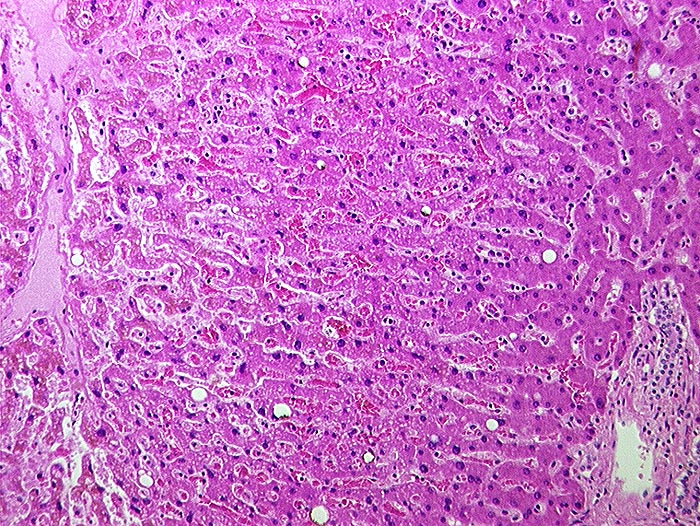

AP/ Subakute Stauung der Leber

Subakute Stauung der Leber

vaskulär / Durchblutungsstörung

Leber, Gallenwege, Pankreas

Leber

Leber HE

Virtuelles Präparat

Pathologischer Befund